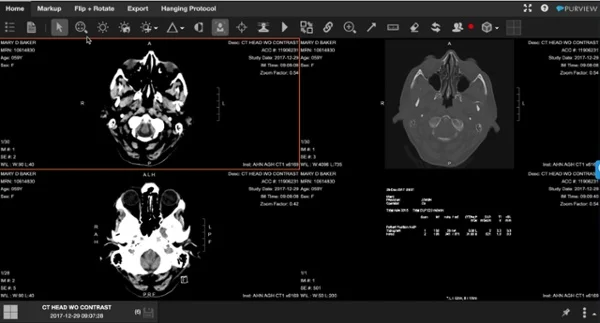

- Key Images: Key images adalah gambar utama atau paling representatif dari suatu studi medis yang digunakan untuk mewakili studi secara keseluruhan. Mereka sering digunakan untuk tujuan referensi cepat, penyimpanan arsip, atau pertukaran informasi antara profesional medis.

- Structured Display: Tampilan grafis yang menampilkan informasi struktur dari laporan medis atau hasil pemeriksaan, seperti peta panas untuk distribusi intensitas radiasi dalam suatu gambar, atau diagram anatomi yang menunjukkan lokasi temuan abnormal.